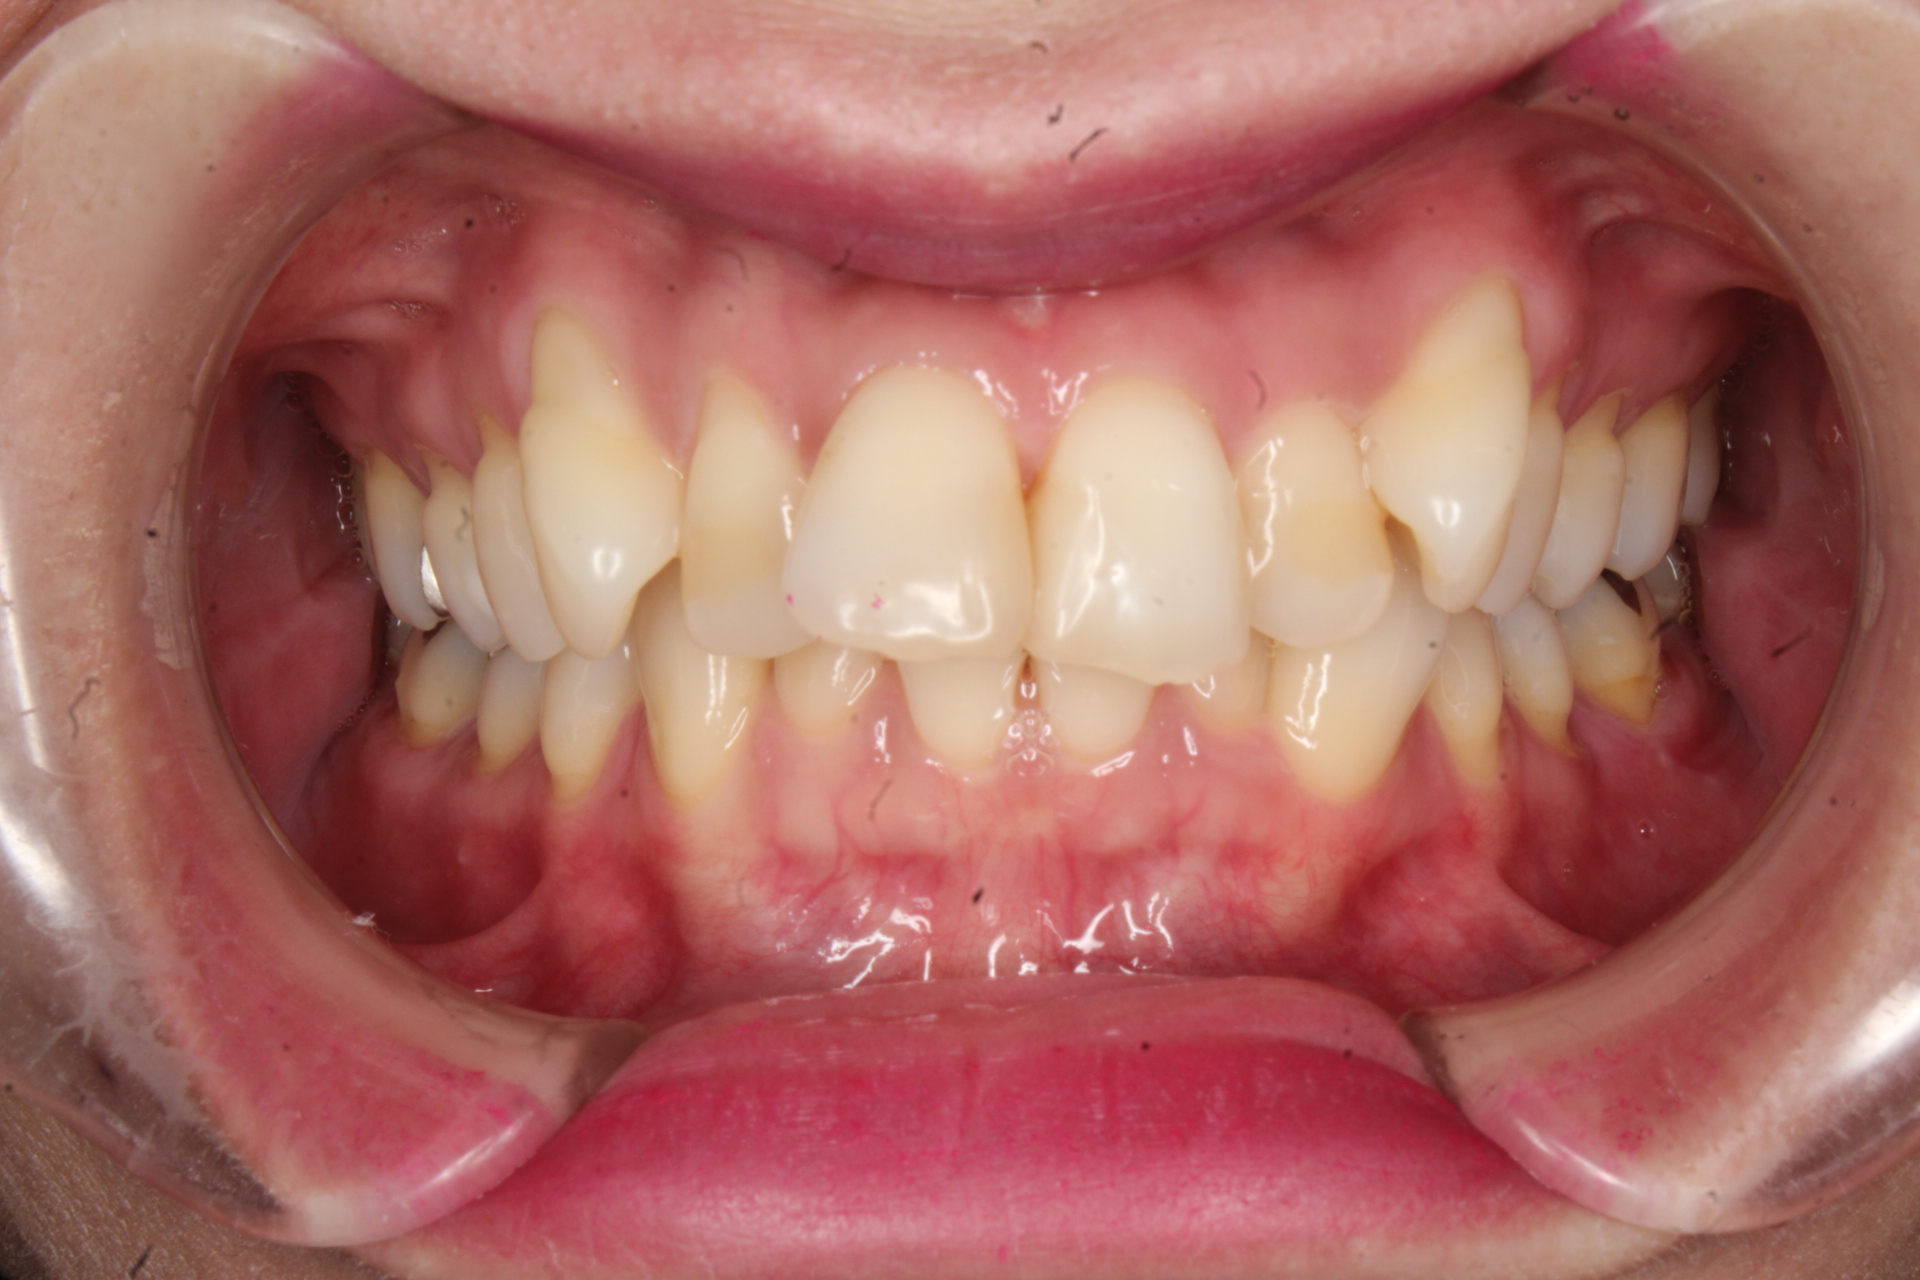

症例 矯正

Before

After

叢生と開咬を治したい

主訴 【主訴】凸凹を治したい・かみ合わせが悪い 【診断・症状】叢生・開咬・下顎劣成長・歯肉退縮あり

治療費用 検査・診断:38,500-/表側矯正治療:1,155,000-(※全て税込)

治療期間 約2年1か月(25回)

抜歯 抜歯:有(上4,3・右下2)

矯正の装置 表側矯正

副作用、リスク 歯肉退縮・歯根吸収・疼痛・咬合の違和感・装置の違和感・正中のズレ